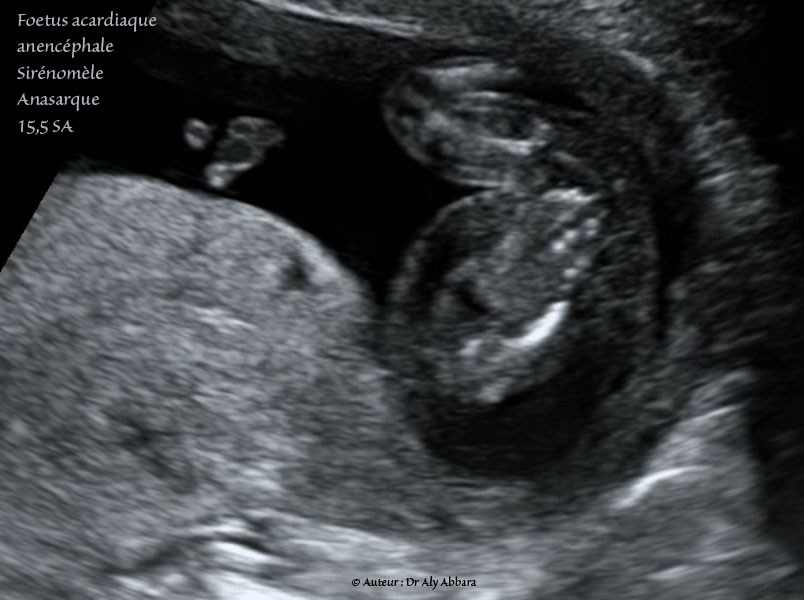

Grossesse gémellaire monochoriale bi-amniotique à 15,5 SA avec un jumeau polymalformé : mouvements actifs du membre inférieur unique.

• Foetus acardiaque : pas structures cardiaques (holoacardius), mais la présence d'une vascularisation provenant de l'autre jumeau normal (jumeau pompe) par le cordon ombilical.

Anencéphale (acrânie - acranius) : absence de structures céphaliques identifiables.

• Amélie des membres supérieurs (absence des deux extrémités supérieures)

• Sirénomélie : un seul membre inférieur comportant deux segments : supérieur avec un fémur, et inférieur contenant deux os longs, mais apodie (absence de pied). Ce membre inférieur est parfois animé par certains mouvements de type flexion - déflexion très réduites.

• Un œdème fœtale généralisé sous-cutané majeur enveloppant ce fœtus acardiaque.

• L'estimation du poids de ce jumeau acardiaque est égale 7,7 grammes pour une longueur de 3,3 cm, contre 118 grammes + 10 % pour le jumeau pompe (donneur normal).